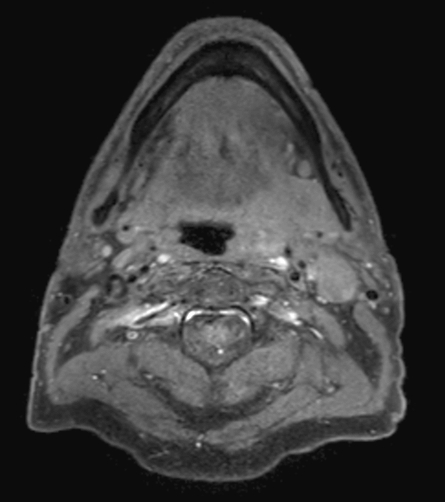

A 75-year-old male with oropharynx squamous cell carcinoma in the left tonsil region with extension into the soft palate, caudal border lower tonsil region, no midline crossing. On the left side in the neck there are also three enlared lymph nodes on level 2 and 3 with central necrosis and signs of limited extracapsular extensionn, T2N2b. Patient underwent MRI simulation in the radiotherapy (5-point) positioning mask in Ingenia MR-RT 3.0T using the Flex coils in combination with integrated Posterior FlexCoverage coil.

T1w TSE mDIXON (water only) post contrast